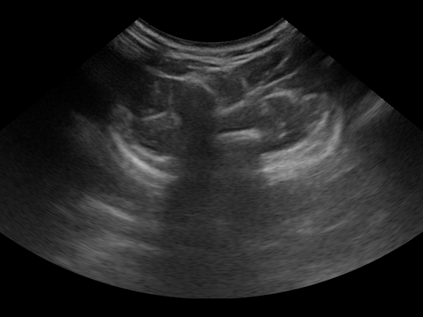

Three-dimensional (3D) freehand ultrasound (US) reconstruction without a tracker can be advantageous over its two-dimensional or tracked counterparts in many clinical applications. In this paper, we propose to estimate 3D spatial transformation between US frames from both past and future 2D images, using feed-forward and recurrent neural networks (RNNs). With the temporally available frames, a further multi-task learning algorithm is proposed to utilise a large number of auxiliary transformation-predicting tasks between them. Using more than 40,000 US frames acquired from 228 scans on 38 forearms of 19 volunteers in a volunteer study, the hold-out test performance is quantified by frame prediction accuracy, volume reconstruction overlap, accumulated tracking error and final drift, based on ground-truth from an optical tracker. The results show the importance of modelling the temporal-spatially correlated input frames as well as output transformations, with further improvement owing to additional past and/or future frames. The best performing model was associated with predicting transformation between moderately-spaced frames, with an interval of less than ten frames at 20 frames per second (fps). Little benefit was observed by adding frames more than one second away from the predicted transformation, with or without LSTM-based RNNs. Interestingly, with the proposed approach, explicit within-sequence loss that encourages consistency in composing transformations or minimises accumulated error may no longer be required. The implementation code and volunteer data will be made publicly available ensuring reproducibility and further research.